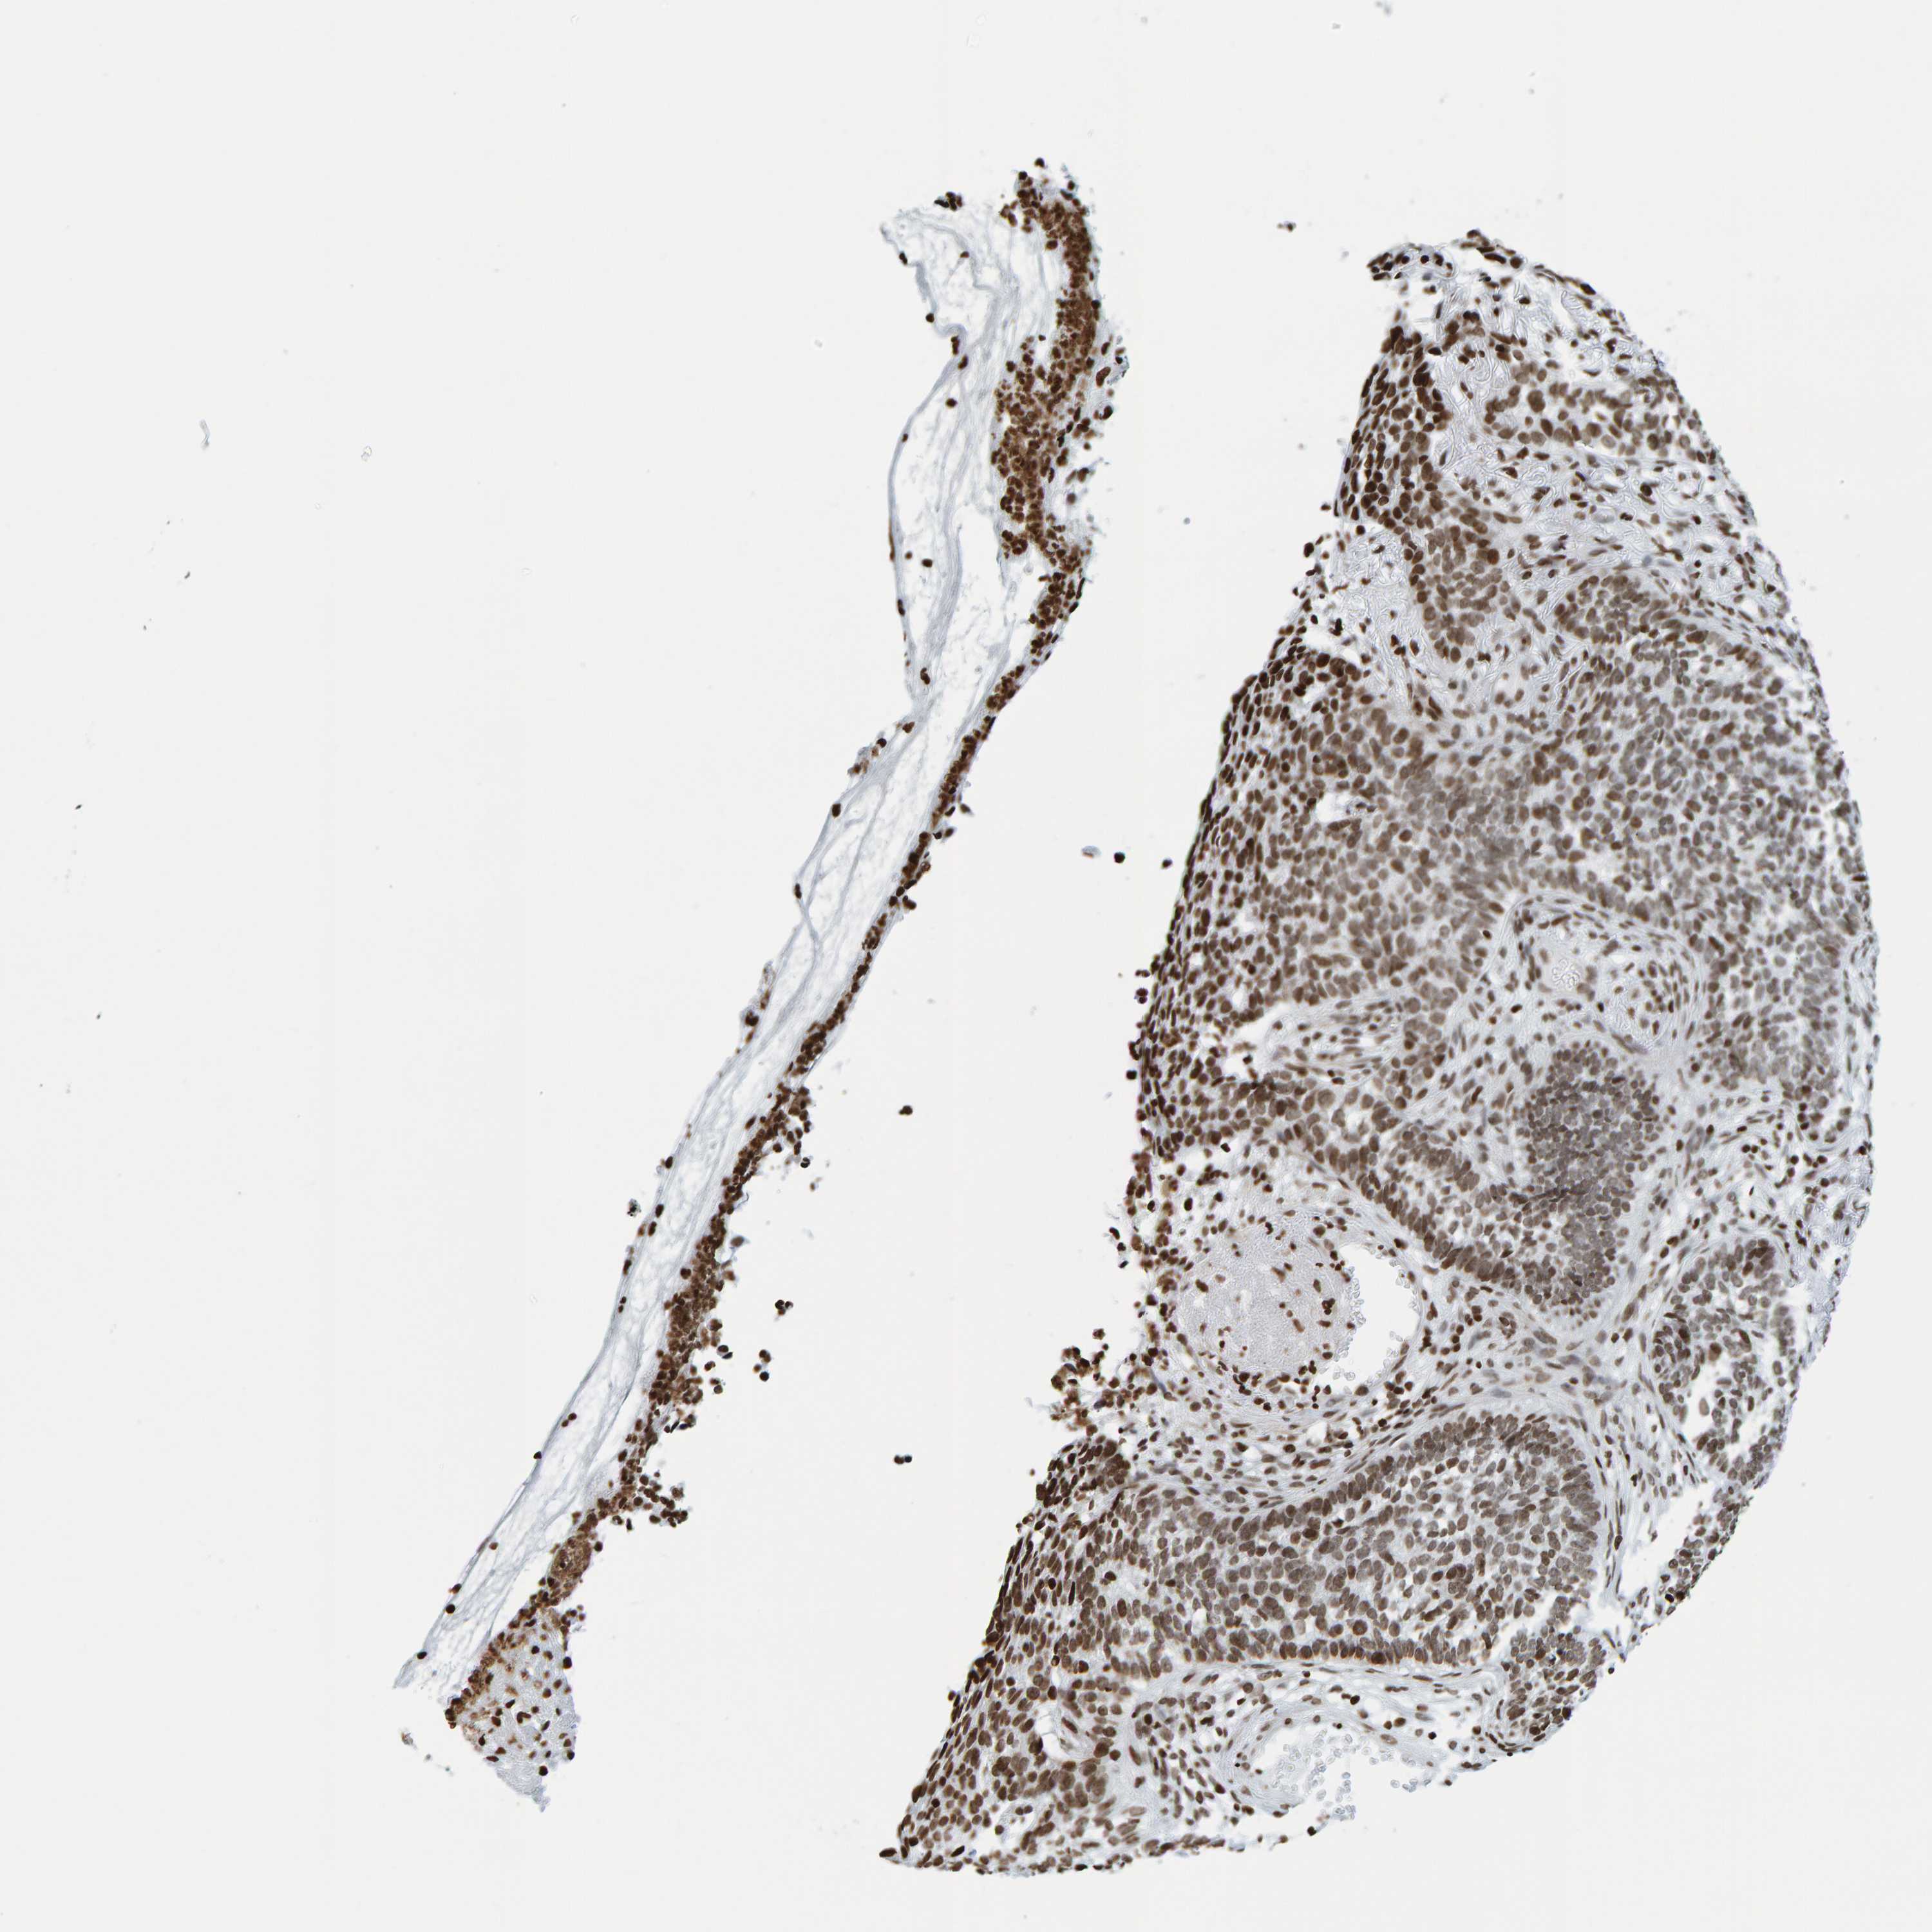

CANCER SKIN CANCER Show tissue menu

SKIN CANCER - Protein expressioni

A mouse-over function shows sample information and annotation data. Click on an image to view it in a full screen mode. Samples can be filtered based on level of antibody staining by selecting one or several of the following categories: high, medium, low and not detected. The assay and annotation is described here.

Each image is clickable and will lead to virtual microscopy that enables deeper exploration of all samples and also displays staining intensity scores, fraction scores and subcellular localization as well as patient and tissue information for each sample.

Antibody CAB019269

Basal cell carcinoma

Squamous cell carcinoma, NOS

Squamous cell carcinoma, metastatic, NOS

Squamous cell carcinoma in situ, NOS

Adnexal tumor, benign